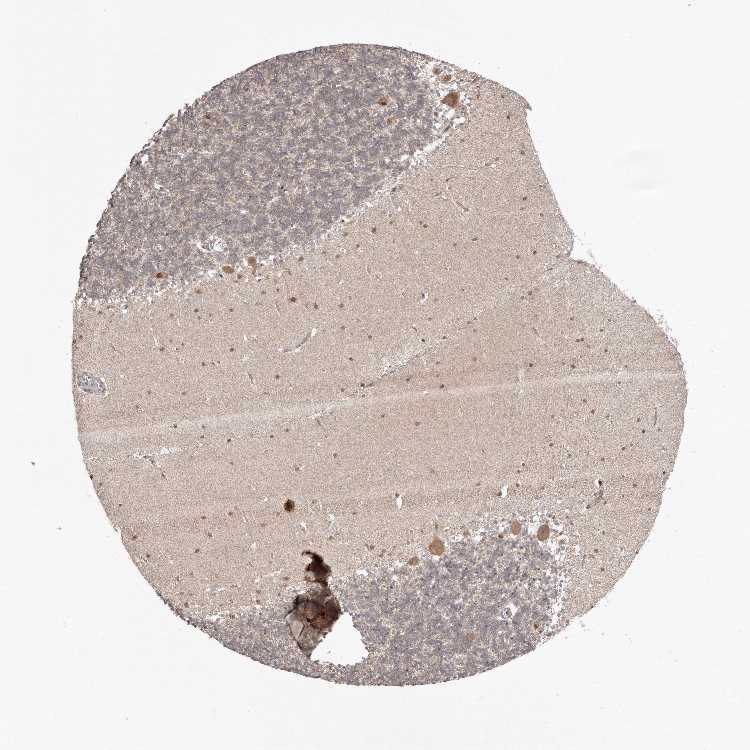

CEREBELLUM - Antibody stainingi

Antibody staining in the annotated cell types in the current human tissue is reported as not detected, low, medium, or high, based on conventional immunohistochemistry profiling in selected tissues. This score is based on the combination of the staining intensity and fraction of stained cells.

Each image is clickable and will lead to virtual microscopy that enables deeper exploration of all samples and also displays staining intensity scores, fraction scores and subcellular localization as well as patient and tissue information for each sample.

Antibody HPA028489

Purkinje cells Medium

Cells in granular layer Low

Cells in molecular layer Medium